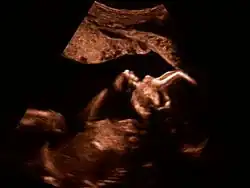

Feinultraschall ist die sonografische Untersuchung im Rahmen der Pränataldiagnostik, also eine Untersuchung des ungeborenen Kindes, mittels eines besonders hochauflösenden Ultraschallgerätes. Synonym werden die Ausdrücke sonografische Feindiagnostik, Organscreening und Fehlbildungsultraschall verwendet.

Der Feinultraschall kann etwa von der 19. bis zur 22. Schwangerschaftswoche durchgeführt werden. Man kann mit ihm einige Entwicklungsstörungen und einige körperliche Besonderheiten beim Kind feststellen bzw. mit einiger Wahrscheinlichkeit ausschließen.